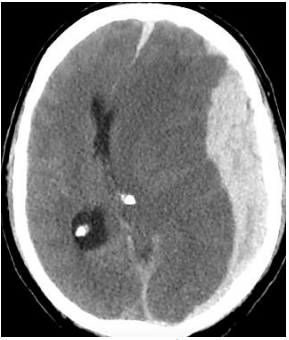

Homem, 70 anos vítima de queda do telhado (3 metros de altura) com trauma craniano seguido de perda da consciência no local. Trazido pelo Serviço de Atendimento Médico de Urgência (SAMU) à sala de trauma de hospital terciário. Admitido pela equipe do trauma em Glasgow 10, anisocoria com pupila esquerda maior que direita. Frente o quadro do paciente e a tomografia de crânio abaixo (figura 4), assinale a alternativa que contenha a conduta correta a ser tomada.

Figura 4 tomografia de crânio sem contraste